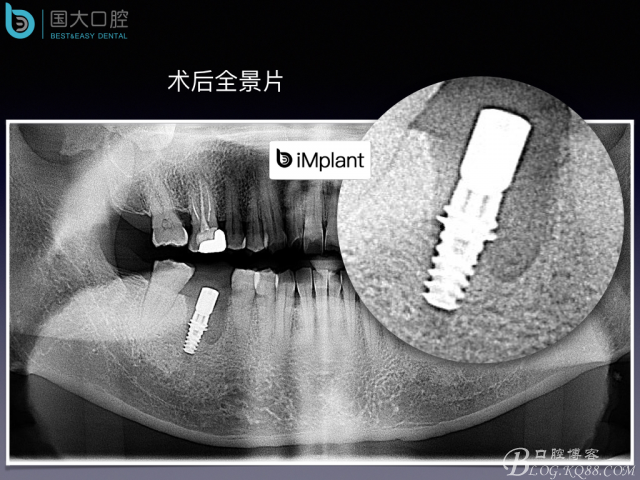

頰側骨壁嚴重缺失,應該如何設計種植位點?

來源于國大口腔 邵現(xiàn)紅醫(yī)生發(fā)表的博文